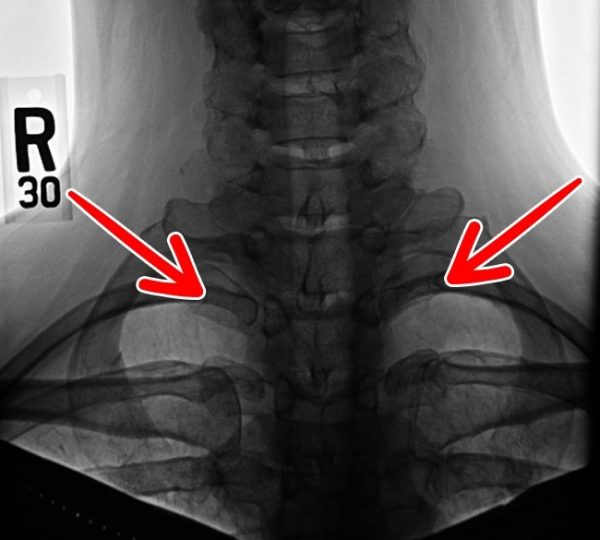

Хүзүүний хавирга

13 дахь хавирга